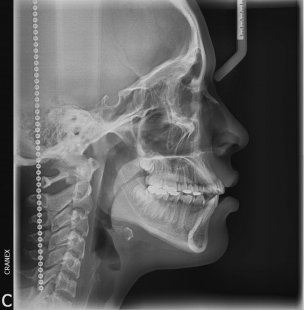

- RX .Lateral Estricta

- RX. Lateral en posición natural de la cabeza (PNC)

- RX .Lateral 7ma vertebra